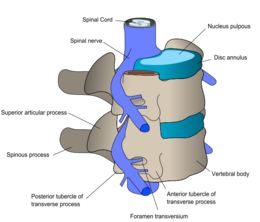

diagram of vertebrae and spinal nerves

Spinal nerves exit the spinal cord between each pair of vertebrae.

At each level of the spinal column, spinal nerves branch off from either side of the spinal cord and exit between a pair of vertebrae, to innervate a specific part of the body. The area of skin innervated by a specific spinal nerve is called a dermatome, and the group of muscles innervated by a single spinal nerve is called a myotome. The part of the spinal cord that was damaged corresponds to the spinal nerves at that level and below. Injuries can be cervical 1–8 (C1–C8), thoracic 1–12 (T1–T12), lumbar 1–5 (L1–L5),[8] or sacral (S1–S5).[9] A person's level of injury is defined as the lowest level of full sensation and function.[10] Paraplegia occurs when the legs are affected by the spinal cord damage (in thoracic, lumbar, or sacral injuries), and tetraplegia occurs when all four limbs are affected (cervical damage).[11]